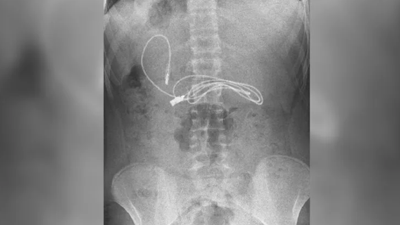

Faslı turistin midesinden çıktı. Polisler şaştı kaldı Türkiye’ye midesindeki 194 adet kapsül halinde bulunan 1 kilo 545 gram reçine esrarı ile giriş yapan Faslı turist Yalova’da yakalandı.

Faslı turistin midesinden iki kiloya yakın esrar çıktı Türkiye’ye midesindeki 194 adet kapsül halinde bulunan 1 kilo 545 gram reçine esrarı ile giriş yapan Faslı turist Yalova’da yakalandı.